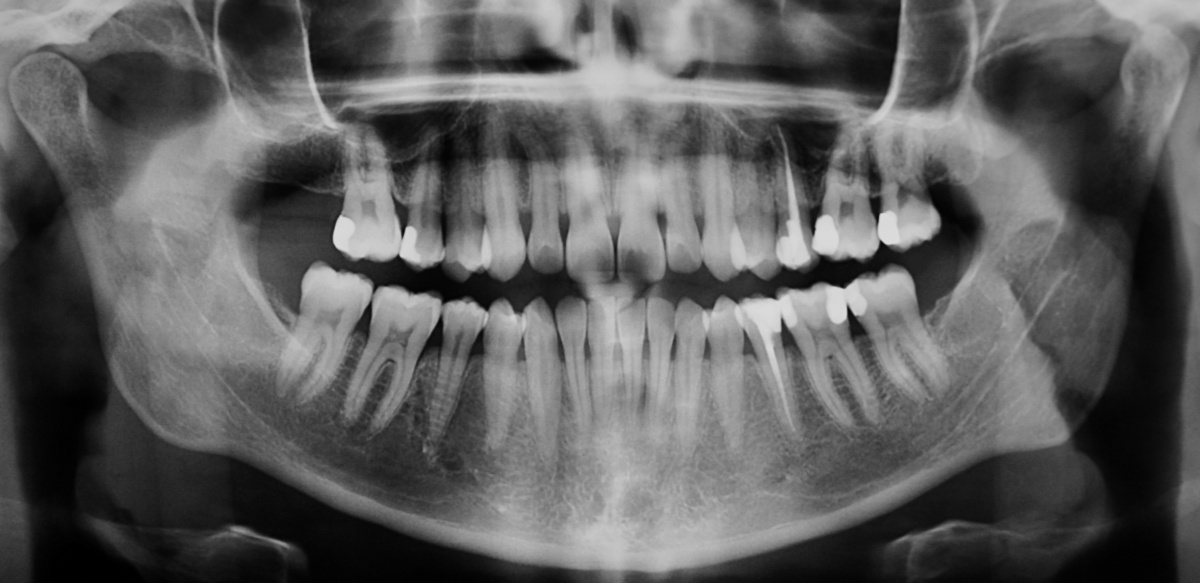

OP, es zeigt sich eine annähernd vollständige

Ausheilung der Resektionshöhle.

Eine 39-jährige Soldatin stellte sich im Januar 2020 mit Druckbeschwerden Regio 22 in unserer Abteilung vor. Wie auch in der vorangegangenen Falldarstellung konnten die Beschwerden mit Druck auf das Vestibulum verstärkt werden. Der Perkussionstest fiel deutlich positiv, der Vitalitätstest hingegen negativ aus. Eine erhöhte Lockerung des Zahnes lag, trotz des eindrucksvollen Röntgenbefundes, nicht vor. Erste Beschwerden traten laut Aussage der Patientin bereits 2014 auf. Das zu diesem Zeitpunkt angefertigte Röntgenbild zeigte keinen signifikanten pathologischen Befund, woraufhin die Situation weiterhin beobachtet wurde. Das aktuell angefertigte Röntgenbild zeigte eine umfangreiche periapikale Osteolyse, welche sich bis zu den Wurzelspitzen 21 und 23 erstreckte. Der Vitalitätstest der beiden benachbarten Zähne fiel positiv aus.

Nach Wurzelfüllung des Zahnes 22, erfolgte die intrasulkuläre Schnittführung mit Entlastungenschnitten mesial der Zähne 21 und 24, um einen ausreichenden Abstand der Schnittränder zum Defekt zu gewährleisten. Bereits während der Lappenbildung imponierte ein umfangreicher Defekt des vestibulären Knochens in Höhe der Wurzelspitze des Zahnes 22. Die Osteolyse dehnte sich bis zu den Wurzeln der Zähne 21 und 23 aus und durchbrach zudem die palatinale und nasale knöcherne Begrenzung. Nach Entfernung des Granulationsgewebes deckten wir den Defekt mit einer resorbierbaren Kollagenmembran (Creos Xenoprotect der Firma Nobel Biocare AB, Göteborg) ab und vernähten den Mukoperiostlappen spannungsfrei.

Der chirurgische Eingriff erfolgte ohne Entfernung der Wurzelspitze des Zahnes 22. Laut der bereits erwähnten Untersuchung von Song et al.[5] lag unter anderem eine Ursache für den Misserfolg einer durchgeführten Wurzelkanalbehandlung zu 8,7 % in einer komplexen anatomischen Struktur und zu 19,7 % in einem übersehenen Wurzelkanal. Das mechanische und chemische Aufbereiten des hier vorgefundenen Wurzelkanals sowie die Obturation waren jedoch auch ohne Resektion der Wurzelspitze problemlos möglich. Wie in Abbildung 11 zu sehen, kam es zu einer intendierten Überfüllung des Wurzelkanals. Daher ist von einer Nischenbildung im apikalen Bereich nicht auszugehen. Das überpresste Wurzelfüllmaterial konnte im Rahmen des anschließenden chirurgischen Eingriffs zuverlässig entfernt werden. Eine zusätzliche Wurzelspitzenresektion hätte in diesem Fall keinen entscheidenden Vorteil gebracht. Kritisch hingegen ist zu betrachten, ob wir der kombiniert endodontisch-chirurgischen Therapie nicht gleich zu Anfang der Behandlungsplanung den Vorzug hätten geben sollen.

palatinal und nasal wurden durch die Osteolyse resorbiert.

Zum Einfluss der Größe apikaler Läsionen auf die Erfolgsraten gibt es auf der einen Seite Studien, die geringere Erfolgsraten bei zunehmender Größe der Läsion zeigen [15]. Andererseits postulieren andere Untersuchungen keinen signifikanten Einfluss der Läsionsgröße auf den Behandlungserfolg [16]. Ausschlaggebend in dieser Kasuistik war, dass die sich die Läsion vermutlich über einen sehr langen Zeitraum (erstes Auftreten der Beschwerden im Jahre 2014) entwickelt hat, was sich wahrscheinlich in der Quantität und Qualität der vorhandenen Mikroorganismen niedergeschlagen haben dürfte. Zum anderen gab das Wiederauftreten der Beschwerden und die neu entstandene Fistelung Grund zur Annahme, dass auch extraradikuläre Bakterien die Entzündungsreaktion fördern. Ein im Jahre 2006 von Nair [17] durchgeführtes Review führt mögliche Keime in periradikulären Läsionen (z. B. Aktinomyzeten) als Ursache für persistierende Infektionen auf. Unterstützt wird das von uns gewählte Vorgehen durch die Studienergebnisse von Ng et al. [18], die eine reduzierte Erfolgswahrscheinlichkeit von nicht-chirurgischen Wurzelkanalbehandlung bei Vorliegen einer periapikalen Osteolyse zeigten. Gleichzeitig reduzierte sich die Prognose mit Zunahme der Läsionsgröße.